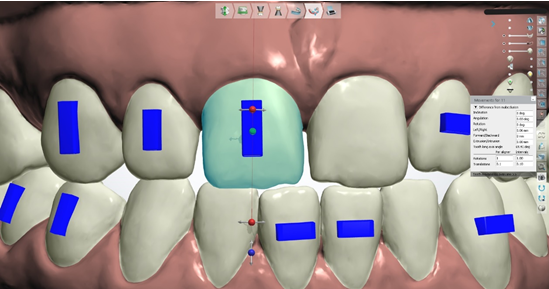

Slika 9. Nakon svih odrađenih faza pristupamo zapravo najkraćoj fazi, a najbitnijoj, samoj prepostavi zuba koja u dizajnu vrlo sliči postavi zuba u mobilnoj protezi u fazi voska. Ono što je naš posao je dovesti zube u položaj koji je ortodont odredio u što je moguće precizniju poziciju poštujući iznose koje je ortodont odredio za pomake poput mezijalizacije, distalizacije, intruzije, ekstruzije, rotacije, angulacije, inklinacije itd. U to možemo biti sigurni jer nam za svaki pomak koji napravimo za pojedini zub sustav izbacuje sa strane iznose pomaka koje napravimo. Ako željena pozicija zuba prelazi vrijednosti koje je ortodont postavio onda je svakak potrebna dodatna konzultacija sa ortodontom da procjeni dali će ekscesivna vrijednost dovesti do neželjene recesije.